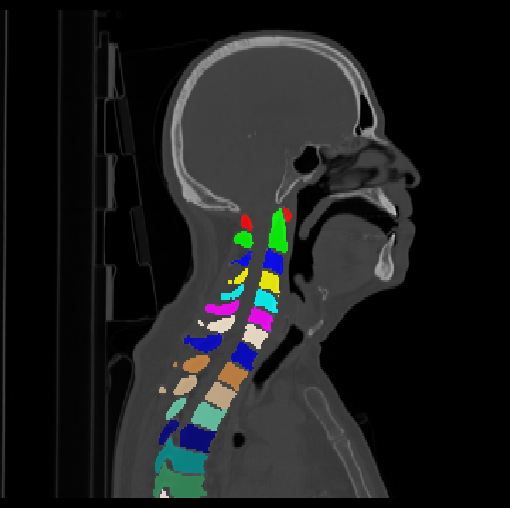

HNSCC-3DCT-RT. This sub-dataset contains three-dimensional (3D) high-resolution fan-beam CT scans collected during pre-, mid-, and post-treatment using a Siemens 16-slice CT scanner with a standard clinical protocol for 31 head-and-neck squamous cell carcinoma (HNSCC) patients (Bejarano et al., 2008). These images are in a DICOM format.

We calculate the two metrics of each vertebra, and the results are reported in Table 2. On the one hand, our experimental results are close to those reported in reference (Sekuboyina et al., 2020) with the same model (nnUnet), verifying the high quality of our annotations. On the other hand, Table 2 shows it is difficult to segment the diseased vertebrae (the DSC of L6 is almost 0). Specifically, the existence of L6 confuses the model, resulting in prediction dislocations (see the last row in Fig. 4). Thus, our labeled dataset, which contains many L6 cases, is very valuable for the diseased vertebrae segmentation (we have stated those cases that are hard for annotation in the readme.txt file). Table 2 illustrates that the model trained with our annotations can achieve good performance on our CTSpine1K dataset but a much worse performance on the VerSe Challenge datasets, which explains there is an obvious domain gap between our annotated dataset and the public dataset. We infer the reason is that the COlONOG dataset is based on an empty stomach and colon, confusing the deep learning model by the changes of air content in the abdomen (see Fig. 3). Therefore, our annotations are a good complement to the existing datasets.

Some visualization results are presented in Fig. 4, where we can observe that the baseline model can achieve excellent segmentation results. Nevertheless, some failed predictions occur when spinal diseases exist, especially sacral lumbarization and lumbar sacralization. Besides, the image’s resolution of Z direction is closely related to the results, and a lower resolution leads to worse results. Maintaining a reasonable performance for a low resolution is a research challenge. Image superresolution (Peng et al., 2020) might be worth exploring.